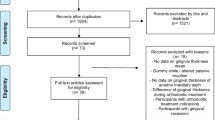

The method consists of four main steps, i.e., optical scanning, surface curvature estimation, region of interest (ROI) definition, and gingival shape analysis. Six different curvature measures and three different diameters were tested for surface curvature estimation on central (n = 78) and interdental ROI (n = 88) of patients with advanced periodontitis to quantify gingiva with a novel gingival shape parameter (GS). The reproducibility was evaluated by repeating the method on two consecutive intraoral scans obtained with a scan-rescan process of the same patient at the same time point (n = 8).